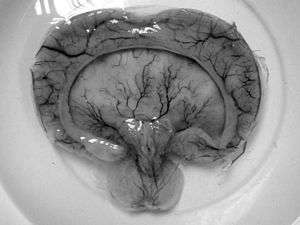

Holoprosencephaly (HPE, once known as arhinencephaly) is a cephalic disorder in which the prosencephalon (the forebrain of the embryo) fails to develop into two hemispheres. Normally, the forebrain is formed and the face begins to develop in the fifth and sixth weeks of human pregnancy. The condition also occurs in other species.

When the embryo's forebrain does not divide to form bilateral cerebral hemispheres (the left and right halves of the brain), it causes defects in the development of the face and in brain structure and function.

There are four classifications of holoprosencephaly.

- Alobar holoprosencephaly, the most serious form, in which the brain fails to separate, is usually associated with severe facial anomalies, including lack of a nose and the eyes merged to a single median structure, see Cyclopia

- Semilobar holoprosencephaly, in which the brain's hemispheres have somewhat divided, is an intermediate form of the disease.

- Lobar holoprosencephaly, in which there is considerable evidence of separate brain hemispheres, is the least severe form. In some cases of lobar holoprosencephaly, the patient's brain may be nearly normal.

- Syntelencephaly, or middle interhemispheric variant of holoprosencephaly (MIHV), in which the posterior frontal lobe and the parietal lobe are not properly separated, but the rostrobasal forebrain properly separates; it is possible that this is not a variant of HPE at all, but is currently classified as such.[2]